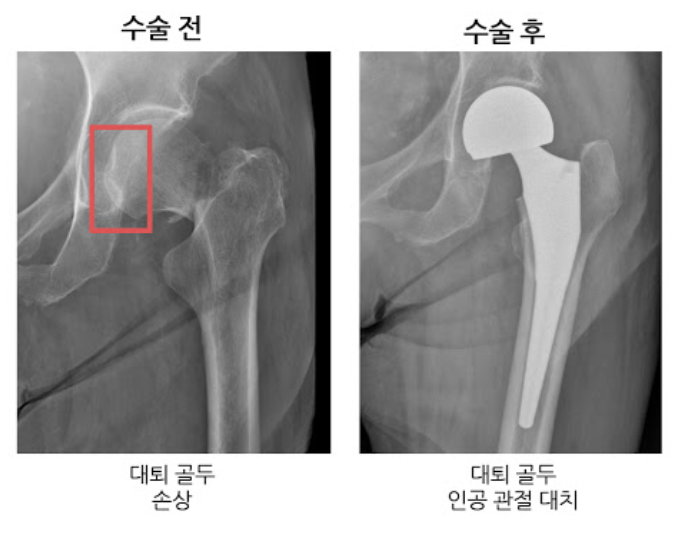

두번쨰로는 대퇴골두에만 인공뼈를 삽입하여 치환시키는 방법과 세번째로는 관절 부분 전체를 인공관절로 바꿔주는 방법이 있습니다. 이 경우에는 심하게 괴사가 된 경우에 사용하는 방법으로 합병증이 적고 기능개선이 우수하다고 알려져 있습니다.